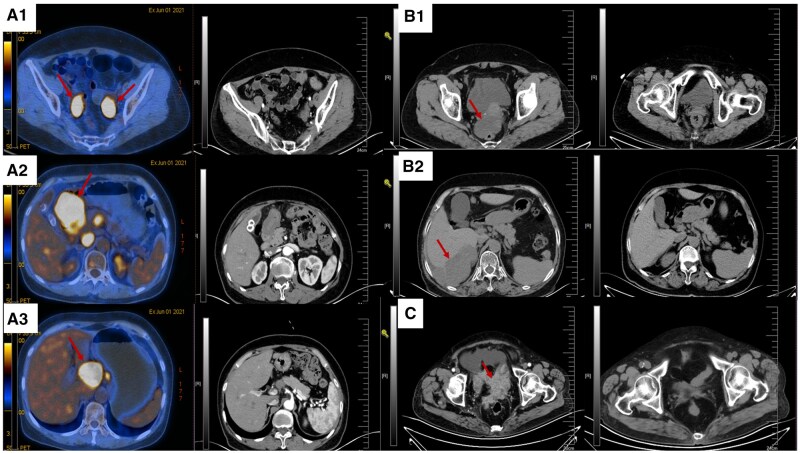

目的:评价老年晚期卵巢癌患者不手术、化疗加维持治疗或不加维持治疗的临床效果。方法:回顾性分析2018 - 2023年我院收治的15例晚期高级别浆液性卵巢癌患者的临床资料。这些患者要么有多种合并症,要么拒绝手术。收集的数据包括患者人口统计学、治疗方案、化疗周期、临床反应、无进展生存期(PFS)和总生存期(OS)。结果:患者年龄中位数为73岁(范围50-86岁)。14例患者接受以铂为基础的化疗联合紫杉醇或脂质体阿霉素,联合或不联合贝伐单抗,疗程3至6个周期。12例获得疾病控制的患者接受了PARP抑制剂维持治疗。总缓解率(ORR)为80.0%,12/15患者达到部分缓解(PR);没有人达到完全缓解。疾病控制率(DCR) 100%。中位PFS1为19.0个月(95% CI, 11.85-26.15),中位PFS2为10个月。3年OS率为65.2%,中位OS为57.0个月(95% CI, 13.00-100.99)。结论:化疗联合或不联合贝伐单抗,再加上PARP抑制剂维持治疗,是老年或不适合手术的晚期卵巢癌患者的可行选择。本研究的结果应该被认为是探索性的,需要通过大规模的研究来验证。

Results: The median age of the patients was 73 years (range, 50-86 years). Fourteen patients received platinum-based chemotherapy combined with paclitaxel or liposomal doxorubicin, with or without bevacizumab, for 3 to 6 cycles. Twelve patients who achieved disease control received PARP inhibitor maintenance therapy. The overall response rate (ORR) was 80.0%, or 12/15 patients achieved partial response (PR); nobody achieved complete response. The disease control rate (DCR) was 100%. The median PFS1 was 19.0 months (95% CI, 11.85-26.15), and the median PFS2 was 10 months. The 3-year OS rate was 65.2%, with a median OS of 57.0 months (95% CI, 13.00-100.99).